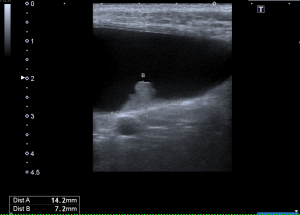

治療させていただいたワンちゃんは、超音波検査で偶然に膀胱腫瘍が見つかりました。膀胱鏡検査、CT検査で精査しましたが、幸いにも初期で転移もありませんでした。尿路全摘出によるQOL低下が懸念されたため、膀胱部分切除と両側の尿管転植を行いました。病理組織学的検査では、移行上皮癌で取り切れているとのことでした。

↑赤いイソギンチャクのようなものが腫瘍です。